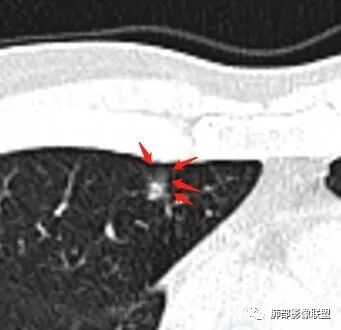

如果实性病变,边缘收缩,可以考虑炎性, 但是边缘有边界清楚GGO,一定要警惕恶性,还有粗短毛刺更要小心撇开其它,看到这个图,除非你怀疑假象,不然就是要考虑腺癌的可能

边界清楚GGO,短毛刺,这要小心瘢痕癌可以多为腺癌复查没变化,与血供有关,属于休眠期张国祯教授的理论:腺瘤样增生、原位癌都属于偏良性,就是没有侵袭性;以后发展——侵袭可以,不变可以,部分可能还会凋亡(比较少)

原位腺癌